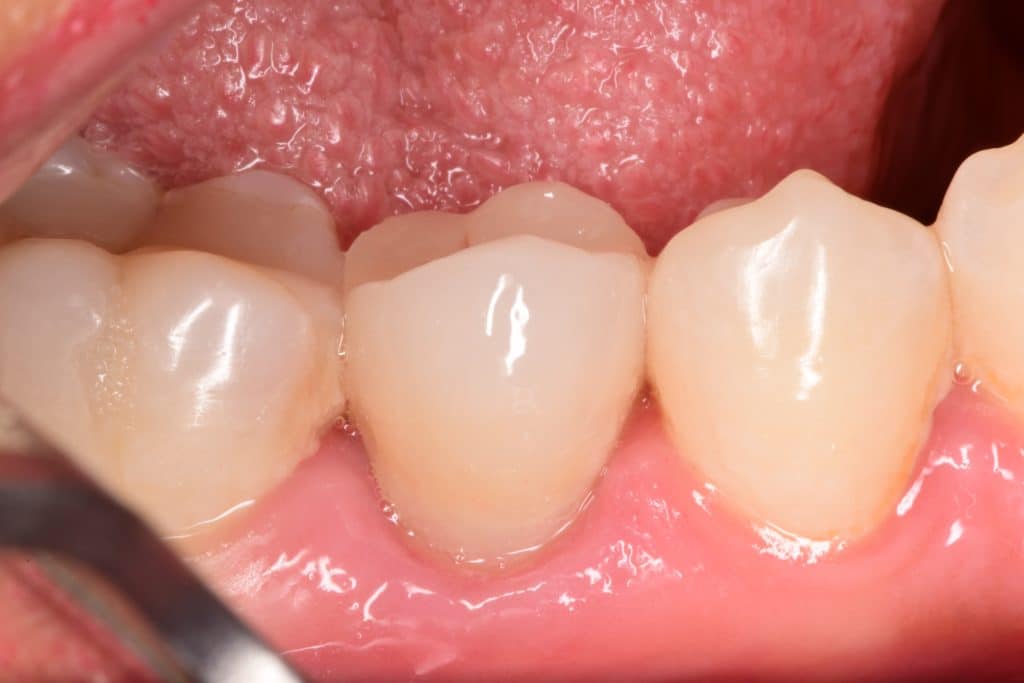

Immediate result after rubberdam removal

Occlusal view

2 weeks later , healing as it should be